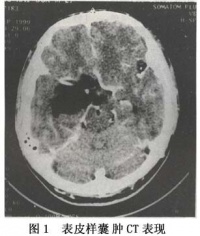

内皮样囊肿CT图